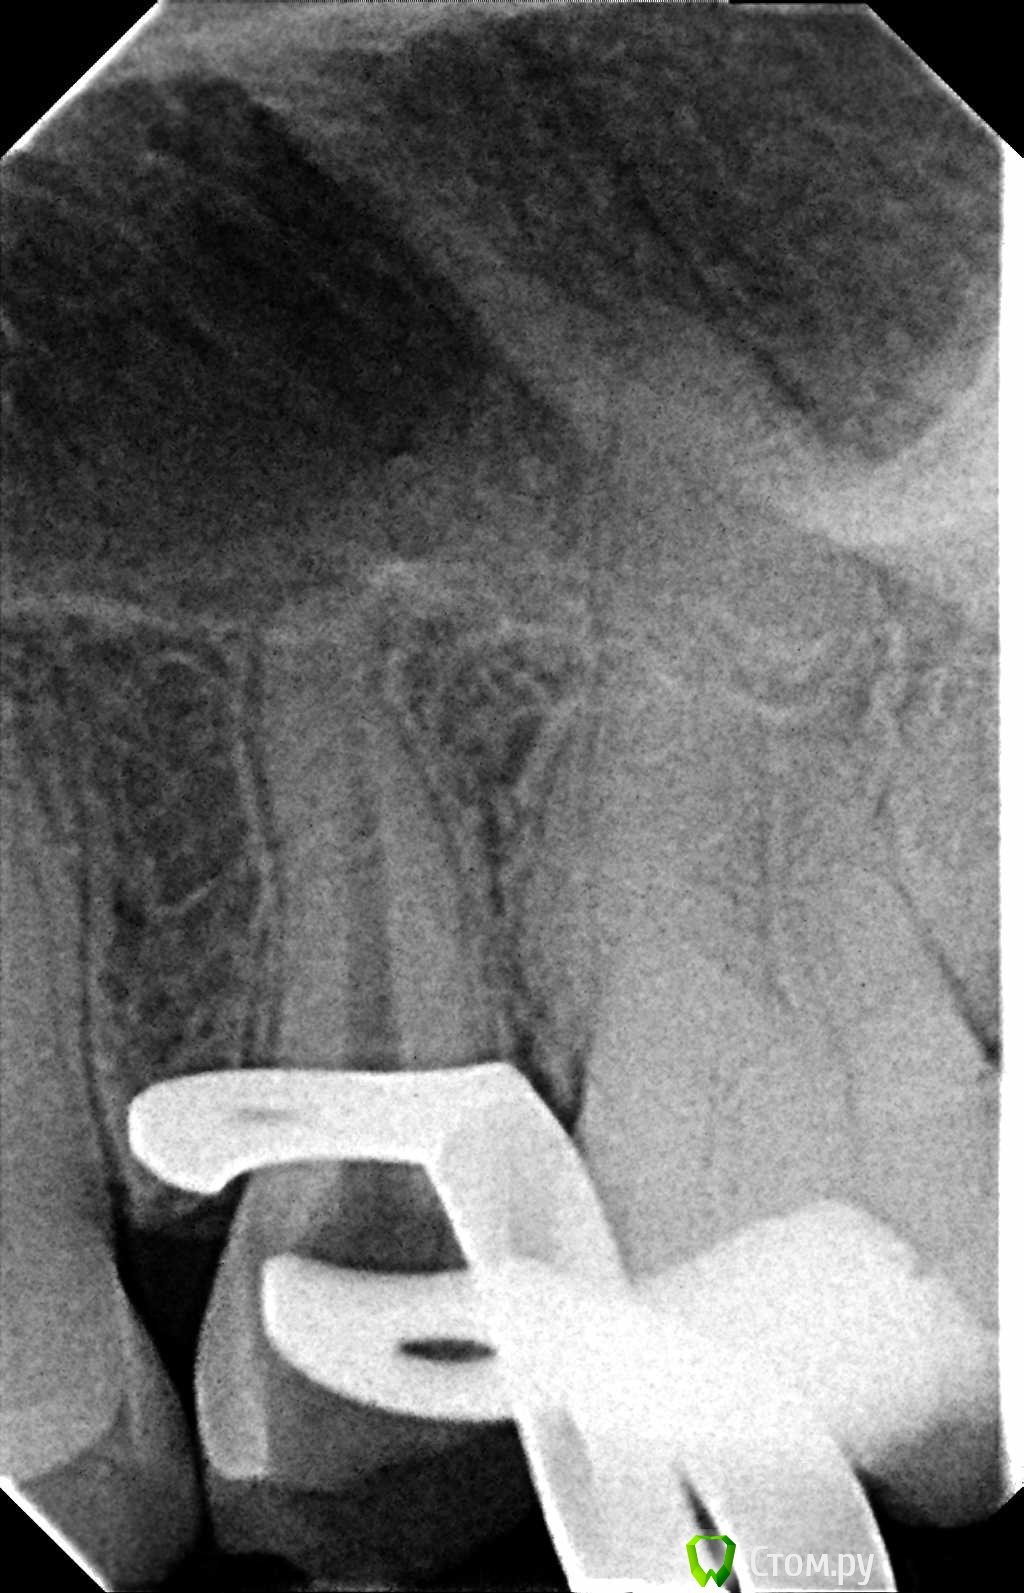

Hans85 Опубликовано 8 января, 2014 Автор Поделиться Опубликовано 8 января, 2014 НУ еще чуток доступа может кому будет интересноПациент - геморная кариозная полость по дистальной поверхности 47,точка сообщения с полостью зуба обнаружилась,традиционный доступ уничтожил бы зуб,пришлось хитрить. 11 Ссылка на комментарий

Hans85 Опубликовано 9 января, 2014 Автор Поделиться Опубликовано 9 января, 2014 (изменено) Так теперь попробуем выстроить нормальную логическую цепочку.Кейс из разряда сам сломал сам доставай-благо канал относительно прямой,времени удаление фрагмента заняло 15-20 минут.Сломал кстати протейпер S2 Изменено 9 января, 2014 пользователем Hans85 8 Ссылка на комментарий

Shaid Опубликовано 9 января, 2014 Поделиться Опубликовано 9 января, 2014 (изменено) Hans85, как извлекли инструмент? Судя по апексу - был риск протолкнуть отломок за апекс. Клевый кейс! Изменено 9 января, 2014 пользователем Shaid Ссылка на комментарий

Hans85 Опубликовано 9 января, 2014 Автор Поделиться Опубликовано 9 января, 2014 Hans85, как извлекли инструмент? Судя по апексу - был риск протолкнуть отломок за апекс. Клевый кейс! Сделал минимально пространство в области торца инструмента 15 U-File чуть расшатал и с водой озвучивал рассчитывая на гидроудар. Ссылка на комментарий